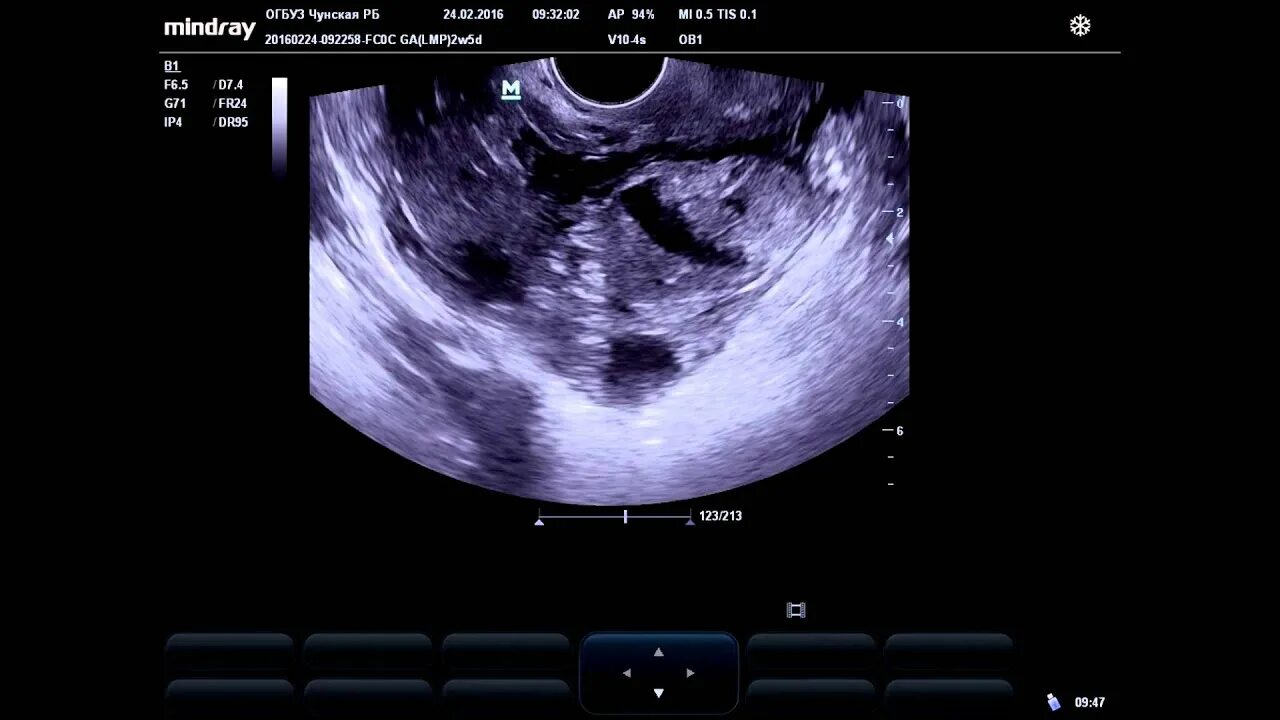

Можно ли на узи увидеть внематочную беременность